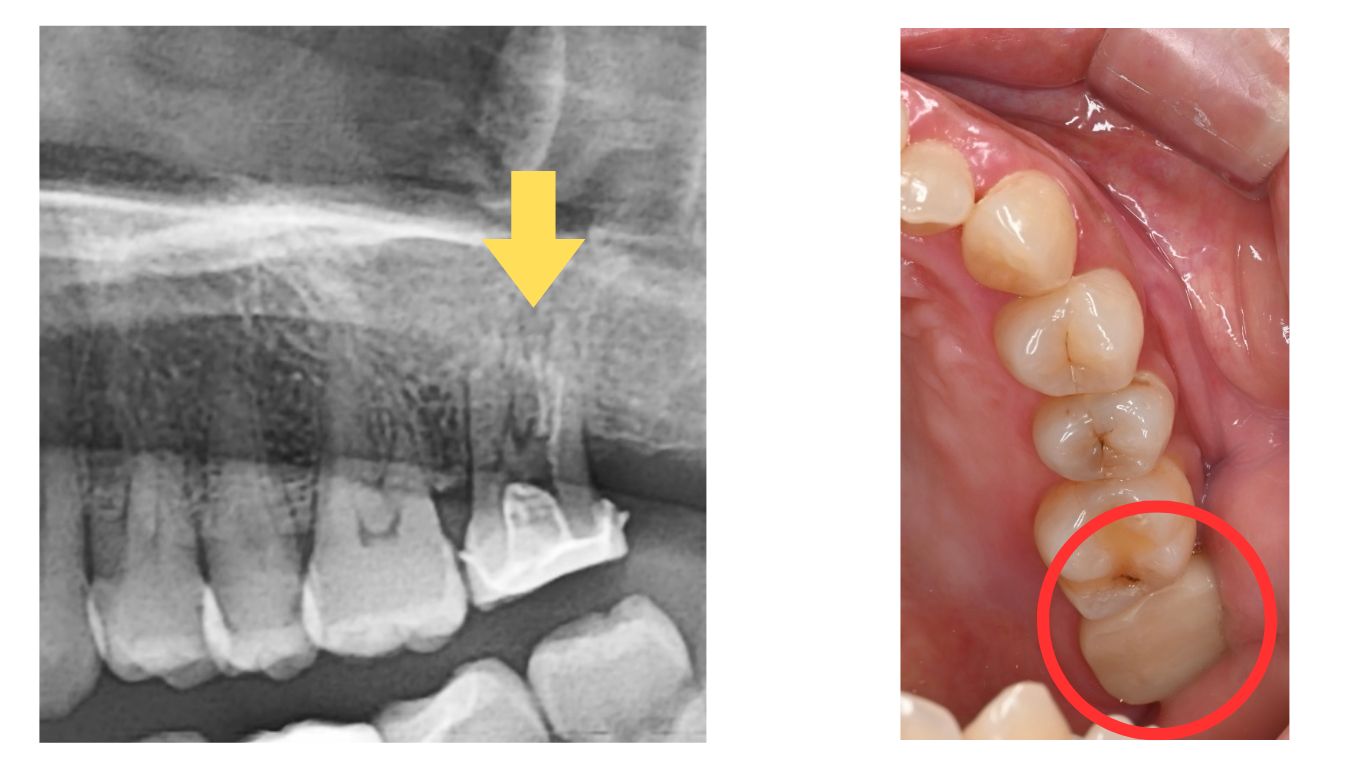

患部のCTを撮影したところ、根尖部(根の先端)に膿が貯まっていることを確認しました。

画像上では、根の先端にある黒く抜けている部分が根尖です。

この状態を根尖性歯周炎(Per)といいます。